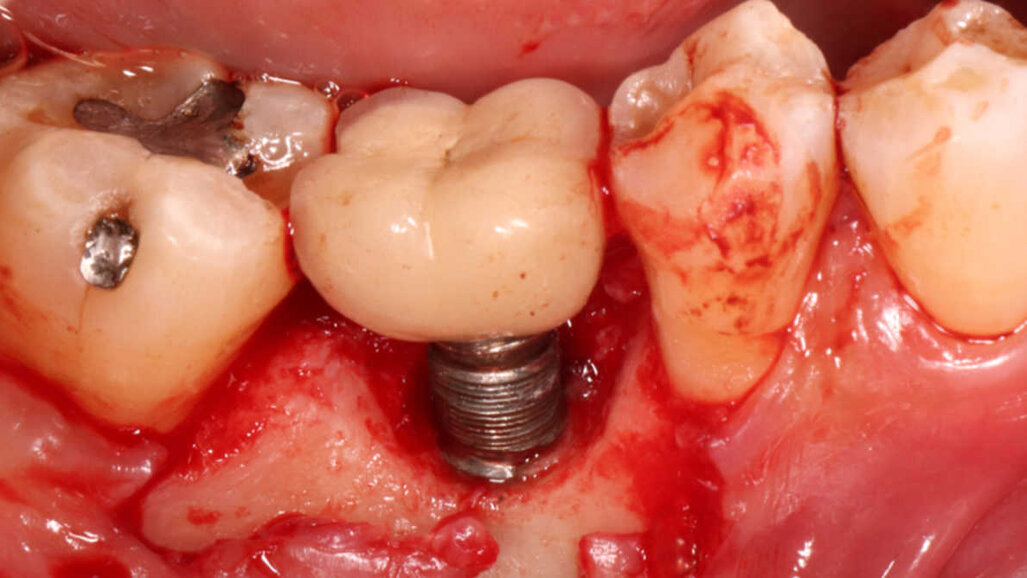

Os pesquisadores descobriram que a falha precoce do implante é normalmente causada pela falta de obtenção ou manutenção da osseointegração, ou superaquecimento ósseo ou contaminação do local. A falha tardia do implante é desencadeada por fraturas, implantes mal posicionados e peri-implantite progressiva. O último causa 81,9% de falhas tardias no implante. A falha precoce do implante resulta em implantes normalmente móveis e fáceis de remover. A falha tardia do implante significa que os implantes podem ser pelo menos parcialmente osseointegrados e, portanto, mais difíceis de remover.

Como opções para a remoção do implante, o estudo determinou extração dentária, brocas de trefina, cirurgia piezo, cirurgia a laser, técnica de catraca com contra-torque (CTRT) e eletrocirurgia. Embora as brocas de trefina pareçam ser o método mais conhecido para remoção de implantes, o método CTRT, isoladamente ou combinado, deve ser a primeira escolha para o dentista devido à sua baixa invasividade.